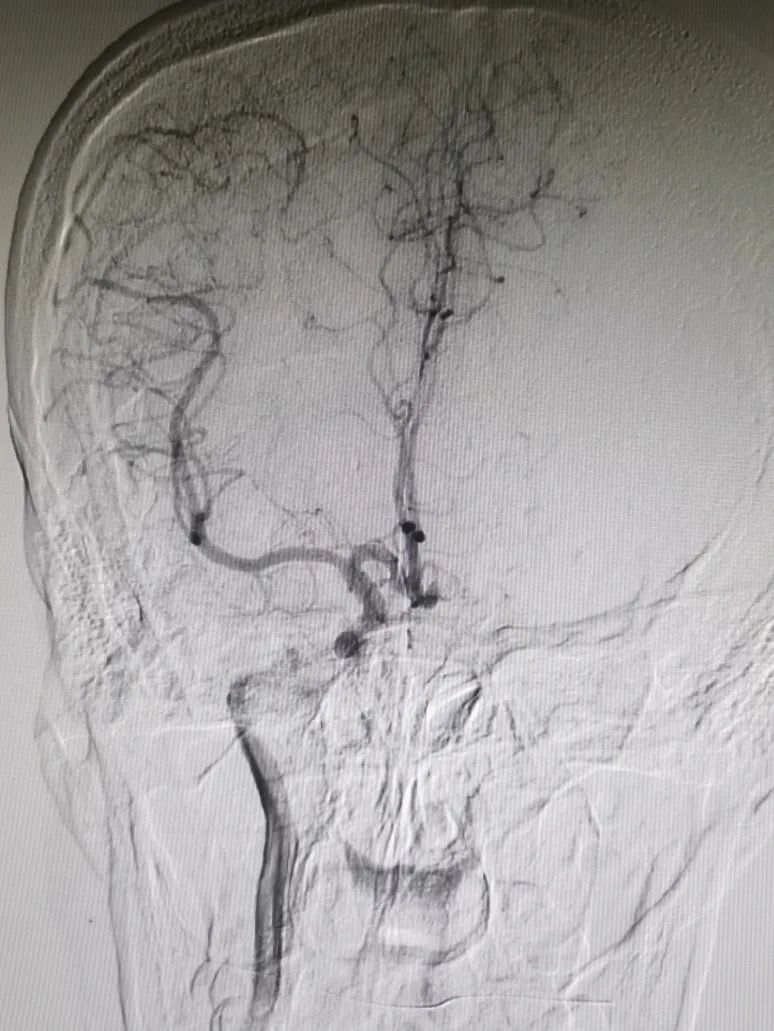

术前造影

造影显示:左侧A1段血流纤细,左侧前循环供血通过右侧A1段及前交通代偿。

左侧颈内动脉末端梭形夹层动脉瘤,2.9mm*3.5mm。